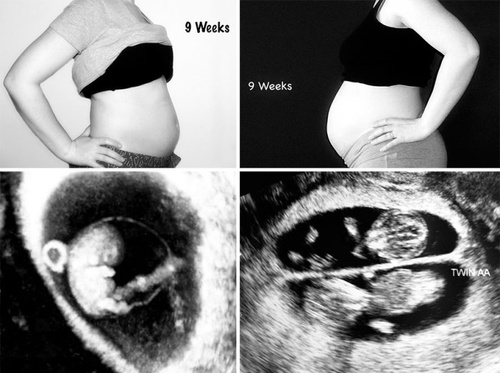

Cum arată o sarcină monofetală, comparativ cu una gemelară. Povestea emoţionantă a femeii care s-a luptat ani buni să poată deveni mamă